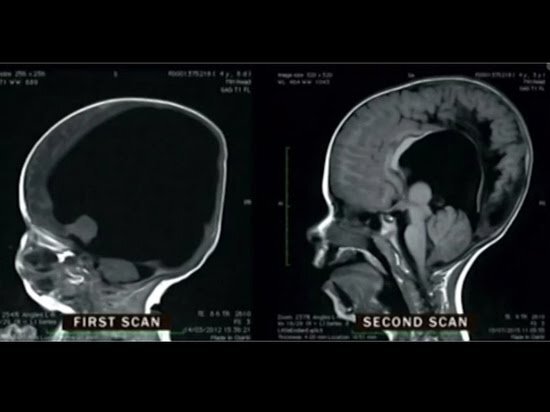

Мальчик по имени Ной, по праву может считать себя чудом природы. Ведь он родился практически без мозга. При рождении у Ноя оказалось всего 2% от нормы объема мозга. Врачи сообщили родителям, что их сын не будет видеть, слышать, говорить, и вероятнее всего умрет. Родители решили оставить ребенка. Как оказалось, остальная часть черепной коробки была заполнена жидкостью. Жидкость откачали и начало происходить необъяснимое. К 6 годам мозг Ноя вырос до 80% от нормы. Он научился ходить и говорить. Стал слышать и видеть. Этот удивительный случай поразил общественность. На что ещё способна природа? Это мы ещё узнаем)

К 6 годам мозг Ноя вырос до 80% от нормы. Он научился ходить и говорить. Стал слышать и видеть.